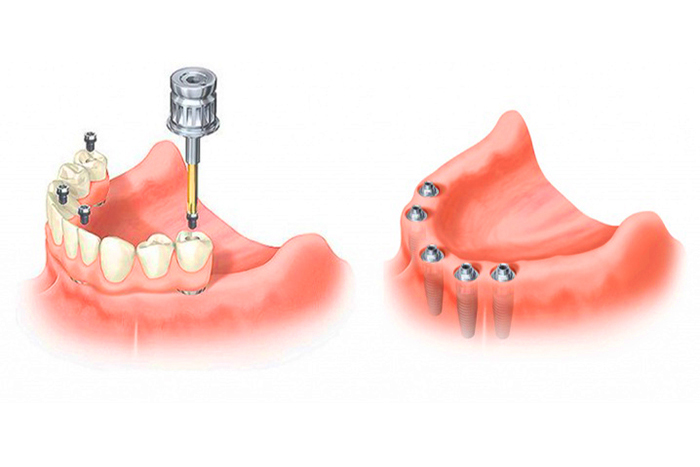

Современные съемные протезы на локаторах: Фото и примеры